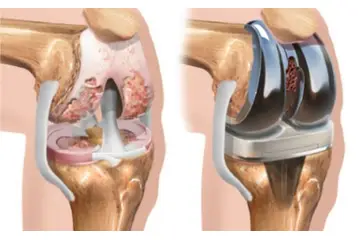

Tedavi Seçenekleri Burun kıkırdak eğriliği tedavisi, hastanın semptomlarına ve durumun ciddiyetine bağlı olarak değişiklik gösterir. Tedavi yöntemleri şunlardır: